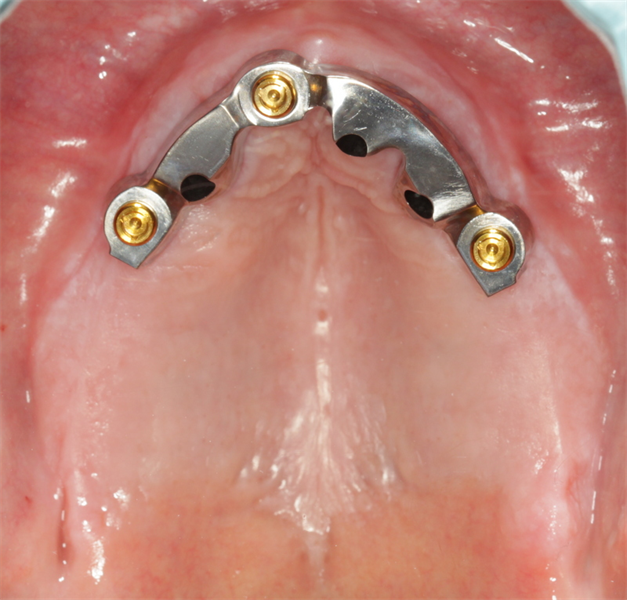

Guidelines for Bar Over dentures

My patient presented with no maxillary restoration and a mandibular one that was in poor condition. Before we even thought about implants, I made a conventional denture and two mandibular FDPs (bridges), which helped me establish a plane of occlusion, tooth position based on esthetics...  Read More